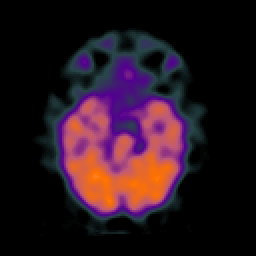

SPECT TC Study #6 -- Slice #19

[Home][Help][Clinical][Tour 1][Tour 2][Tour 3] Slice 19